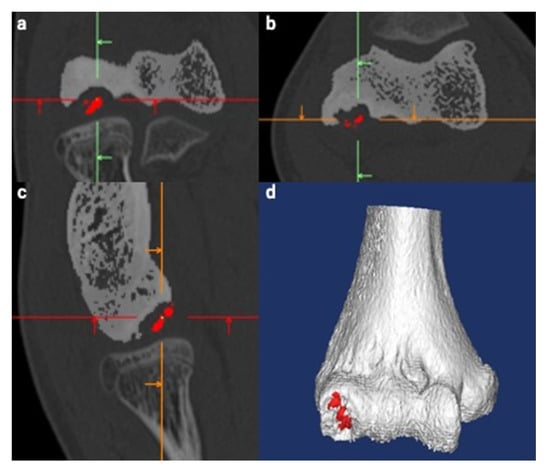

2.3. Creation of 3D Models

Figure 3. Creation of a three-dimensional (3D) computed tomography (CT) model of the humerus. The same procedure as used with magnetic resonance imaging was used. The segmented subchondral bone (SSB) was defined as the lesion whose continuity to the floor was lost in all three planes. The separate SSB model was created manually and is displayed in red for better visualization. Green, red and orange lines are the reference lines correspond to sagittal, axial and coronal, respectively. (a) Coronal view. (b) Axial view. (c) Sagittal view. (d) Reconstructed 3D image of the humerus.